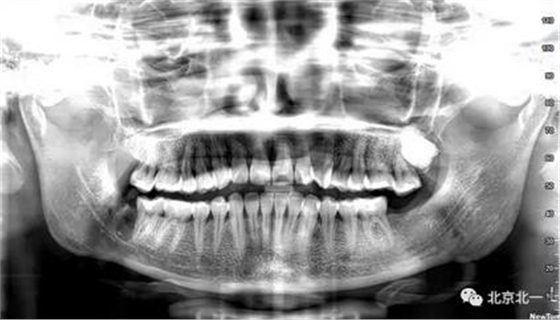

圖十二:拍片確認無誤。

總結:單純拍片看牙齒并不復雜, 通過微創(chuàng)拔牙有絲分裂可以避免傷及神經, 本病例特殊之處在于牙齒顏色和骨顏色無法區(qū)別。導致去骨或者分牙比較茫然, 不可大意,以及磨牙的手感和去骨的手感一致時,兩者不好區(qū)分。 只能偏向保守, 多角度拍片再三確認后予以安全拔除。 另外CBCT模式上看智齒位置也有誤差,醫(yī)師要根據經驗調整,特別是在這種哪里是骨,哪里是牙的情況,不能盲目大范圍去骨導致術中骨折。

另外重點:強調無菌,注意不要污染手術,位置深,創(chuàng)傷大,完全是一個口腔頜面部手術, 按照外科原則準備。 該病例手術后口服消炎藥,并沒有輸液抗炎。 腫脹不明顯和書中完全無菌操作, 用生理鹽水冷卻的專用種植機分牙,拒絕管路水污染, 無敲擊以及術后引流片引流有很大關系。